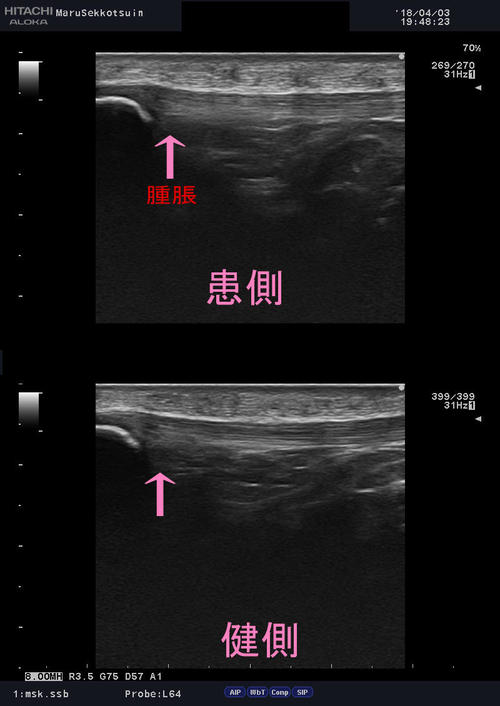

いつもの通り、しっかり問診、触診を行い、確認でエコー検査。

エコー画像でも膝蓋靭帯上に不鮮明像が診られ、炎症、腫脹を確認。